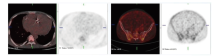

男性患者, 37岁, 于2020-08-21因“ 腹胀2月余, 双下肢水肿1月余, 活动后气促20天” 入院。患者于2020年6月无明显诱因出现腹胀, 7月出现双下肢水肿, 晨起时明显, 至广东省人民医院心内科门诊就诊, 2020-07-29心脏彩超示:考虑缩窄性心包炎, 建议结合心脏CT检查; 轻度二尖瓣返流; 中度三尖瓣返流; 中度肺高压; 少-中量心包积液。2020年8初患者出现活动后气促, 2020-08-12心脏CT示:心脏起搏器置入术后改变。心包、心脏及肺动脉周围弥漫性病变, 考虑恶性肿瘤性病变, 建议进一步18F-FDG-PET/CT检查及穿刺活检; 大量心包积液, 腹腔积液。2020-08-18行PET/CT示:(1)房室沟、心缘、下腔静脉入口旁软组织影, 双侧胸膜病变、右侧肺门淋巴结、多处骨质病变, 以上病变糖代谢增高, 考虑淋巴瘤并以上浸润。(2)大量心包积液, 大量腹腔积液, 下腔静脉入口管腔扩张, 提示心包填塞可能, 注意心功能情况。(3)18F-FDG-PET/CT体部扫描余部位未见恶性肿瘤代谢影像。(4)心脏起搏器置入术后。心脏占位及骨质改变见图1。

| 图1 2020-08-18 PET/CT检查心脏占位及骨质改变Fig.1 PET/CT examination of cardiac mass and bone lesions (2020-08-18) |

入院后治疗:结合PET/CT、病理、骨穿结果, 诊断为伯基特淋巴瘤, Ⅳ B期, 国际预后指数(international prognostic index, IPI)4分。于2020-09-07开始予甲强龙40 mg qd减瘤治疗。于2020-09-11予CDOP(cyclophosphamide, pegylated liposomal doxorubicin, vincristine, prednisone, 环磷酰胺、盐酸多柔比星脂质体、长春新碱、泼尼松)(50%)化疗。后续于2020-09-27、2020-10-23、2020-11-18分别予CD20单抗(利妥昔单抗)联合CODOXM-A(cyclophosphamide, vincristine, epirubicin, methotrexate, 环磷酰胺, 长春新碱, 盐酸多柔比星脂质体, 甲氨蝶呤)、CODOXM-B(ifosfamide, etoposide, cytarabine, 异环磷酰胺, 依托泊苷, 阿糖胞苷)、CODOXM-A方案治疗。因浆膜腔积液为使用大剂量甲氨喋呤禁忌症之一, 患者持续存在大量腹水, A方案中以替莫唑胺替代甲氨喋呤。根据方案每疗程行腰椎穿刺+鞘内注射预防中枢侵犯。2周期化疗后复查PET/CT(2020-11-18)示:心脏及纵隔大血管周围病变明显缩小, 糖代谢减低(SUVmax 2.0); 双侧胸膜病变及右肺门淋巴结代谢较前减低(SUVmax 1.5), 多处骨代谢增高灶未见显示; 心包积液, 心脏增大, 双心房明显; 右侧胸腔积液; 大量腹腔积液, 下腔静脉入口管腔扩张。靶病灶达完全缓解, 但患者持续存在大量腹水。心脏及纵隔大血管病变见图2。

瘤和继发性肿瘤。原发性心脏淋巴瘤不仅位于或主要位于心脏和心包的淋巴瘤, 可以发生于心脏的任何部位, 以右心尤以右房多见, 肿瘤可向心腔内生长, 可累及心肌、心包, 引起心律失常和心包积液, 也可侵犯心脏临近大血管, 包括上、下腔静脉, 导致回流障碍, 需与肉瘤相鉴别。而转移性心脏肿瘤最常累及心包, 其次为心肌, 也可累及心内膜。该患者基线PET/CT提示病灶主要位于心肌, 累及部分心包, 代谢水平明显升高, 考虑恶性, 需与肉瘤相鉴别。

旁述:根据美国国立综合肿瘤网络(National Comprehensive Cancer Network, NCCN)指南, 高危伯基特淋巴瘤首选CODOXM-A/IVAC(cyclophosphamide, doxorubicin, vincristine, methotrexate/ifosfamide, etoposide, high dose cytarabine, 环磷酰胺、阿霉素、长春新碱、甲氨蝶呤/异环磷酰胺、依托泊苷、高剂量阿糖胞苷)联合CD20单抗交替治疗4程, 年轻患者经化疗后预后好, 客观缓解率(objective response rate, ORR)达93%, 完全缓解率(complete response rate, CRR)达91%, 3年总生存率达76%[8]。该患者2周期治疗后PET/CT提示心脏及纵隔大血管周围病变明显缩小(图2), SUVmax 2.0, Deauville评分3, 虽然仍有大量腹水, 但多次腹水病理细胞学并未见肿瘤, 腹水与肿瘤无关。按照2014 Lugano评价标准[9], 疗效评价CR, 且外周血ctDNA检测阴性。